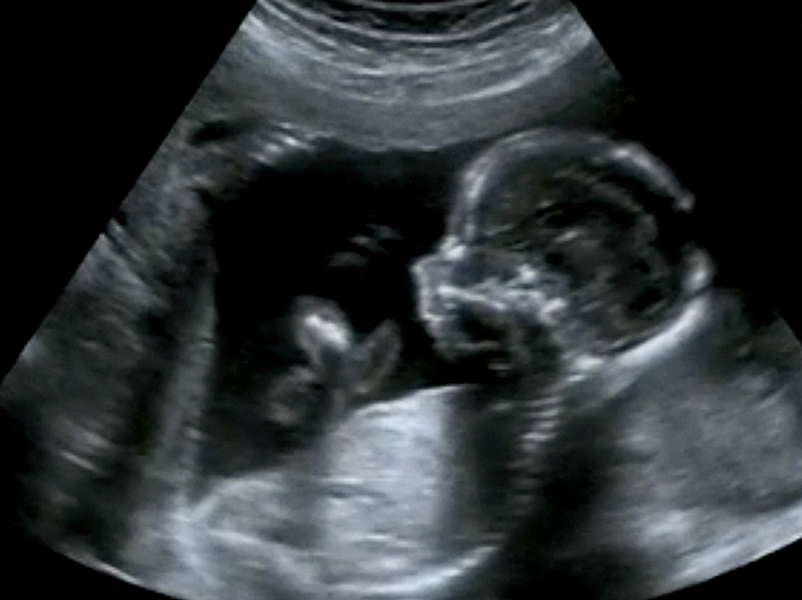

L’endométriose touche une femme sur dix en France. Si son diagnostic est posé un peu plus facilement depuis quelques années, des zones d’ombre persistent. Maladie complexe, elle peut entraîner une errance médicale et des douleurs chroniques impactant les personnes socialement, physiquement et psychologiquement. Cette maladie peut aussi affecter les personnes souhaitant un enfant, et doit être prise en compte dans le suivi médical.